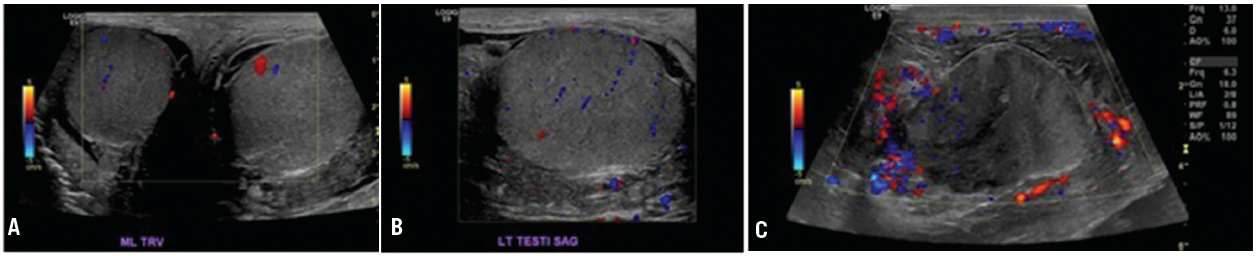

Christopher Cooper, RN, MS; Arpan Patel, MD, PGY-1; Alex Rico, MD

A 65-year-old male presented with a 1-week history of left-sided testicular pain.